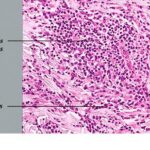

The amount of inflammatory infiltrate in tumorigenic melanomas varies. As a rule, early invasive malignant and many in situ melanomas show a bandlike inflammatory infiltrate, often intermingled with melanophages, at the base of the tumor. In tumors that extend deep into the dermis, the inflammatory infiltrate is quite variable, but it is often only slight to moderate rather than pronounced. Lymphocytes extending among tumor cells are often associated with morphologic evidence of damage to individual tumor cells (apoptosis). These tumor-infiltrating lymphocytes (TILs) have been shown to have independent favorable prognostic significance . The infiltrate is a predominantly T-cell response . TILs extracted from melanomas (mostly metastatic cases) may be cytotoxic and may be directed against immunogenic melanoma-associated antigens . |

Mitotic figures are usually present in the lesional cells of the dermal and epidermal compartments of tumorigenic melanomas [they are present in the epidermal lesional cells in about one third of nontumorigenic melanomas and in the dermal compartment of 85% of tumorigenic melanomas . Mitoses may also be seen in adjacent hyperplastic keratinocytes. The nuclei of these hyperplastic epidermal keratinocytes may be enlarged with prominent nucleoli, although they are not irregular or hyperchromatic. In contrast, mitotic figures are rarely seen in |

benign nevi other than Spitz nevi, and even in the latter lesions the rate is usually low or zero . |